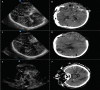

Point-of-care Cranial Ultrasound in a Hemicraniectomy Patient